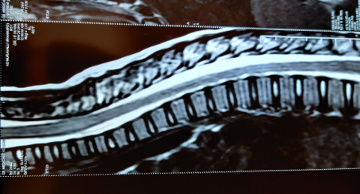

5years old boy with normal development history came with features of altered sensorium and frequent seizures. He went into status epilepticus requiring multiple antiepileptic medications and was ventilated for 7 days. His MRI brain and spine was suggestive of acute disseminated encephalomyelitis(ADEM). The antibodies for NMOSD(NMO and anti-MOG antibodies) were negative.He was treated with injection methylprednisolone and IVIG(immunoglobulin). Now after discharge he has become as normal as before.